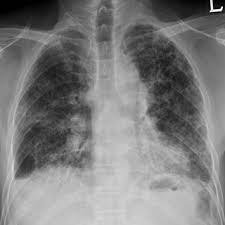

Asbestosis Radiology Reference Article Radiopaedia Org

Asbestosis Radiology Reference Article Radiopaedia Org from prod-images-static.radiopaedia.org

Gejala asbestosis mungkin tidak berkembang sehingga 20 tahun setelah terdedah, menunda rawatan.berpotensi. Asbestos terdiri dari serat silikat mineral dengan komposisi kimiawi yang berbeda. 3,5,9,23 pengobatan bersifat paliatif, beberapa obat yang digunakan diantaranya: Asbes sendiri merupakan serat silikat tahan panas yang banyak digunakan dalam berbagai industri, pelapis lantai, dan atap, terutama sebelum tahun 1970. Istilah asbestosis pertama kali dikemukakan oleh cooke pada 1927, setelah pada 1906 dilaporkan kasus kematian akibat asbestos. Pengertian asbestosis adalah pneumokoniosis yang disebabkan oleh akumulasi pajanan serat asbestos. Gejala, penyebab, diagnosis, dan pengobatan. Asbes adalah suatu jenis mineral yang biasa digunakan untuk pemasangan lantai atau atap bangunan.